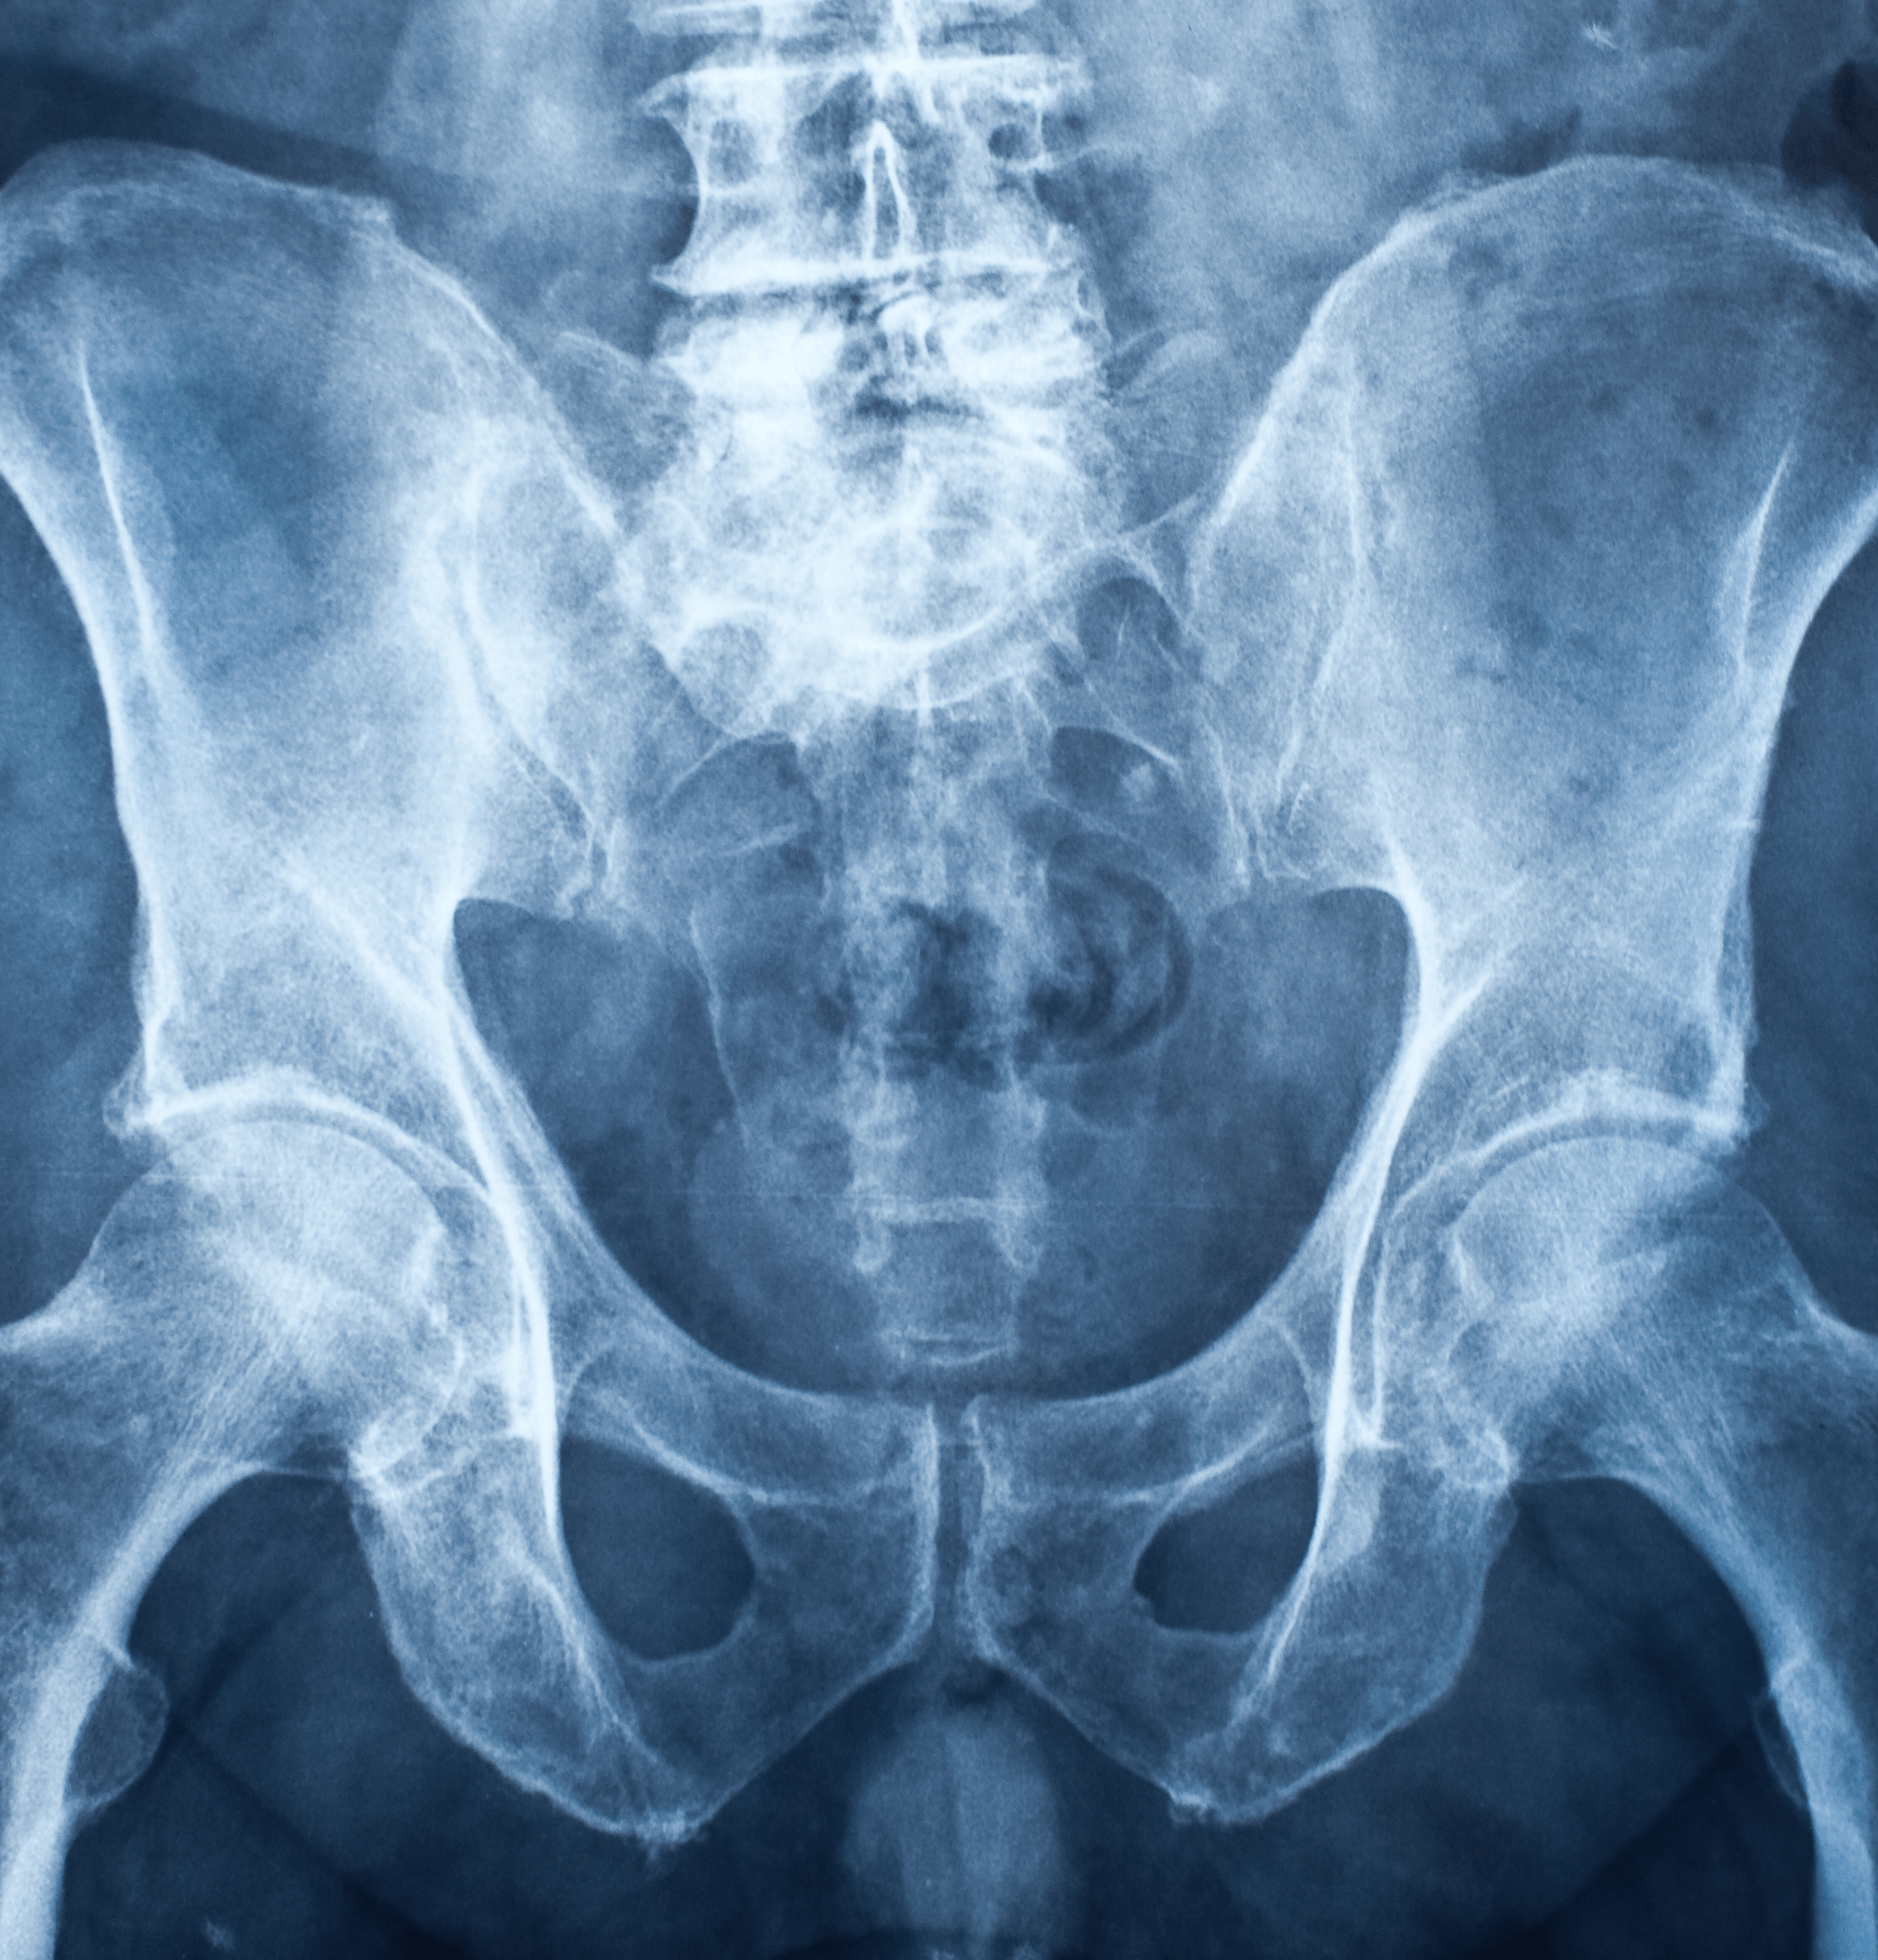

Che cos'è la Radiografia del Femore?

La radiografia del femore, o RX femore, è un esame diagnostico che utilizza i raggi X per ottenere immagini dettagliate dell'osso femorale.

Questo esame permette di visualizzare chiaramente le strutture ossee del femore, evidenziando eventuali fratture, lesioni o anomalie.

L'esame viene condotto utilizzando un fascio di raggi X che attraversa il femore e si imprime su una pellicola o un sensore digitale, creando un'immagine dell'osso.